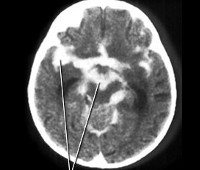

• Методы нейровизуализации. КТ, МРТ, МСКТ головного мозга выявляют диффузные неспецифические изменения белого вещества. Позволяют диагностировать инсульт, интракраниальные кровоизлияния, исключить очаговую патологию мозга (опухоль, кисту).